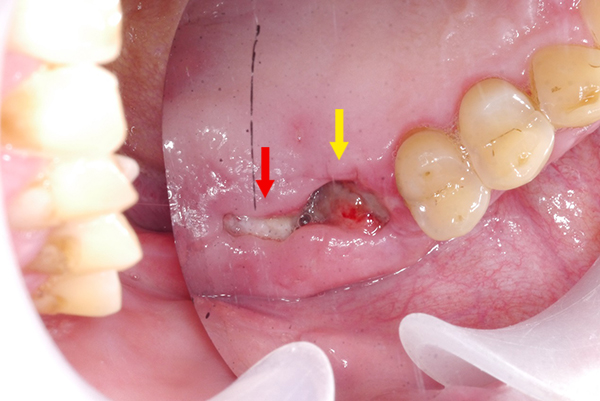

第一大臼齒(黃色箭頭)及第二大臼齒(紅色箭頭)拔牙患者。第二大臼齒區放置膠原蛋白敷料,第一大臼齒區未放置。一周後可見第二大臼齒(紅色箭頭)復原更迅速,傷口大小僅有第一大臼齒(黃色箭頭)一半以下,且傷口平整,復原良好。

紅色箭頭:(噴砂前)菸垢及檳榔垢嚴重堆積。

黃色箭頭:(噴砂後)牙齒牙根表面乾淨,醫師得以仔細檢查牙周病以及植體感染源。